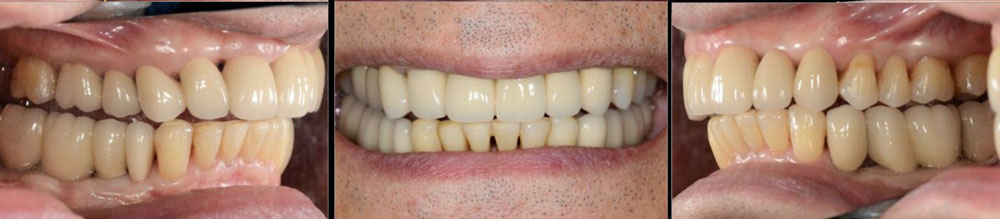

治療後01

治療後02

治療後03

治療後04

治療後05